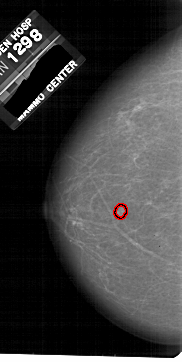

A_1812_1.LEFT_MLO

LEFT_MLO LINES 5206 PIXELS_PER_LINE 2821 BITS_PER_PIXEL 12 RESOLUTION 43.5 OVERLAY

FILE: A_1812_1.LEFT_MLO.OVERLAY

TOTAL_ABNORMALITIES 1

ABNORMALITY 1

LESION_TYPE MASS SHAPE LOBULATED MARGINS MICROLOBULATED

ASSESSMENT 4

SUBTLETY 3

PATHOLOGY BENIGN

TOTAL_OUTLINES 1

BOUNDARY